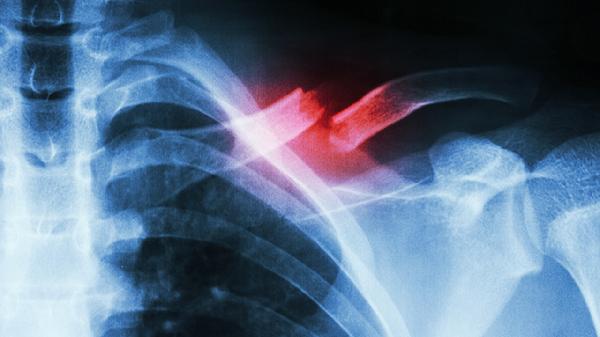

肋骨骨折兩根一般需要住院7-14天,具體時(shí)間與骨折嚴(yán)重程度、是否合并其他損傷、患者年齡及恢復(fù)情況等因素有關(guān)。

肋骨骨折兩根的住院時(shí)間主要取決于骨折的穩(wěn)定性和并發(fā)癥風(fēng)險(xiǎn)。若骨折端無(wú)明顯移位且未損傷胸膜或內(nèi)臟,通常住院7-10天即可完成疼痛控制與初步愈合觀(guān)察。此期間需通過(guò)胸帶固定、口服非甾體抗炎藥如布洛芬緩釋膠囊緩解疼痛,并配合呼吸訓(xùn)練預(yù)防肺部感染。若骨折伴隨血?dú)庑鼗蚍未靷炔l(fā)癥,住院時(shí)間可能延長(zhǎng)至10-14天,需進(jìn)行胸腔閉式引流、吸氧等干預(yù),直至生命體征平穩(wěn)。老年患者或存在骨質(zhì)疏松等基礎(chǔ)疾病者,愈合速度較慢,住院周期可能接近14天。住院期間醫(yī)生會(huì)定期復(fù)查胸部X線(xiàn)或CT,評(píng)估骨折對(duì)位情況及并發(fā)癥改善程度。